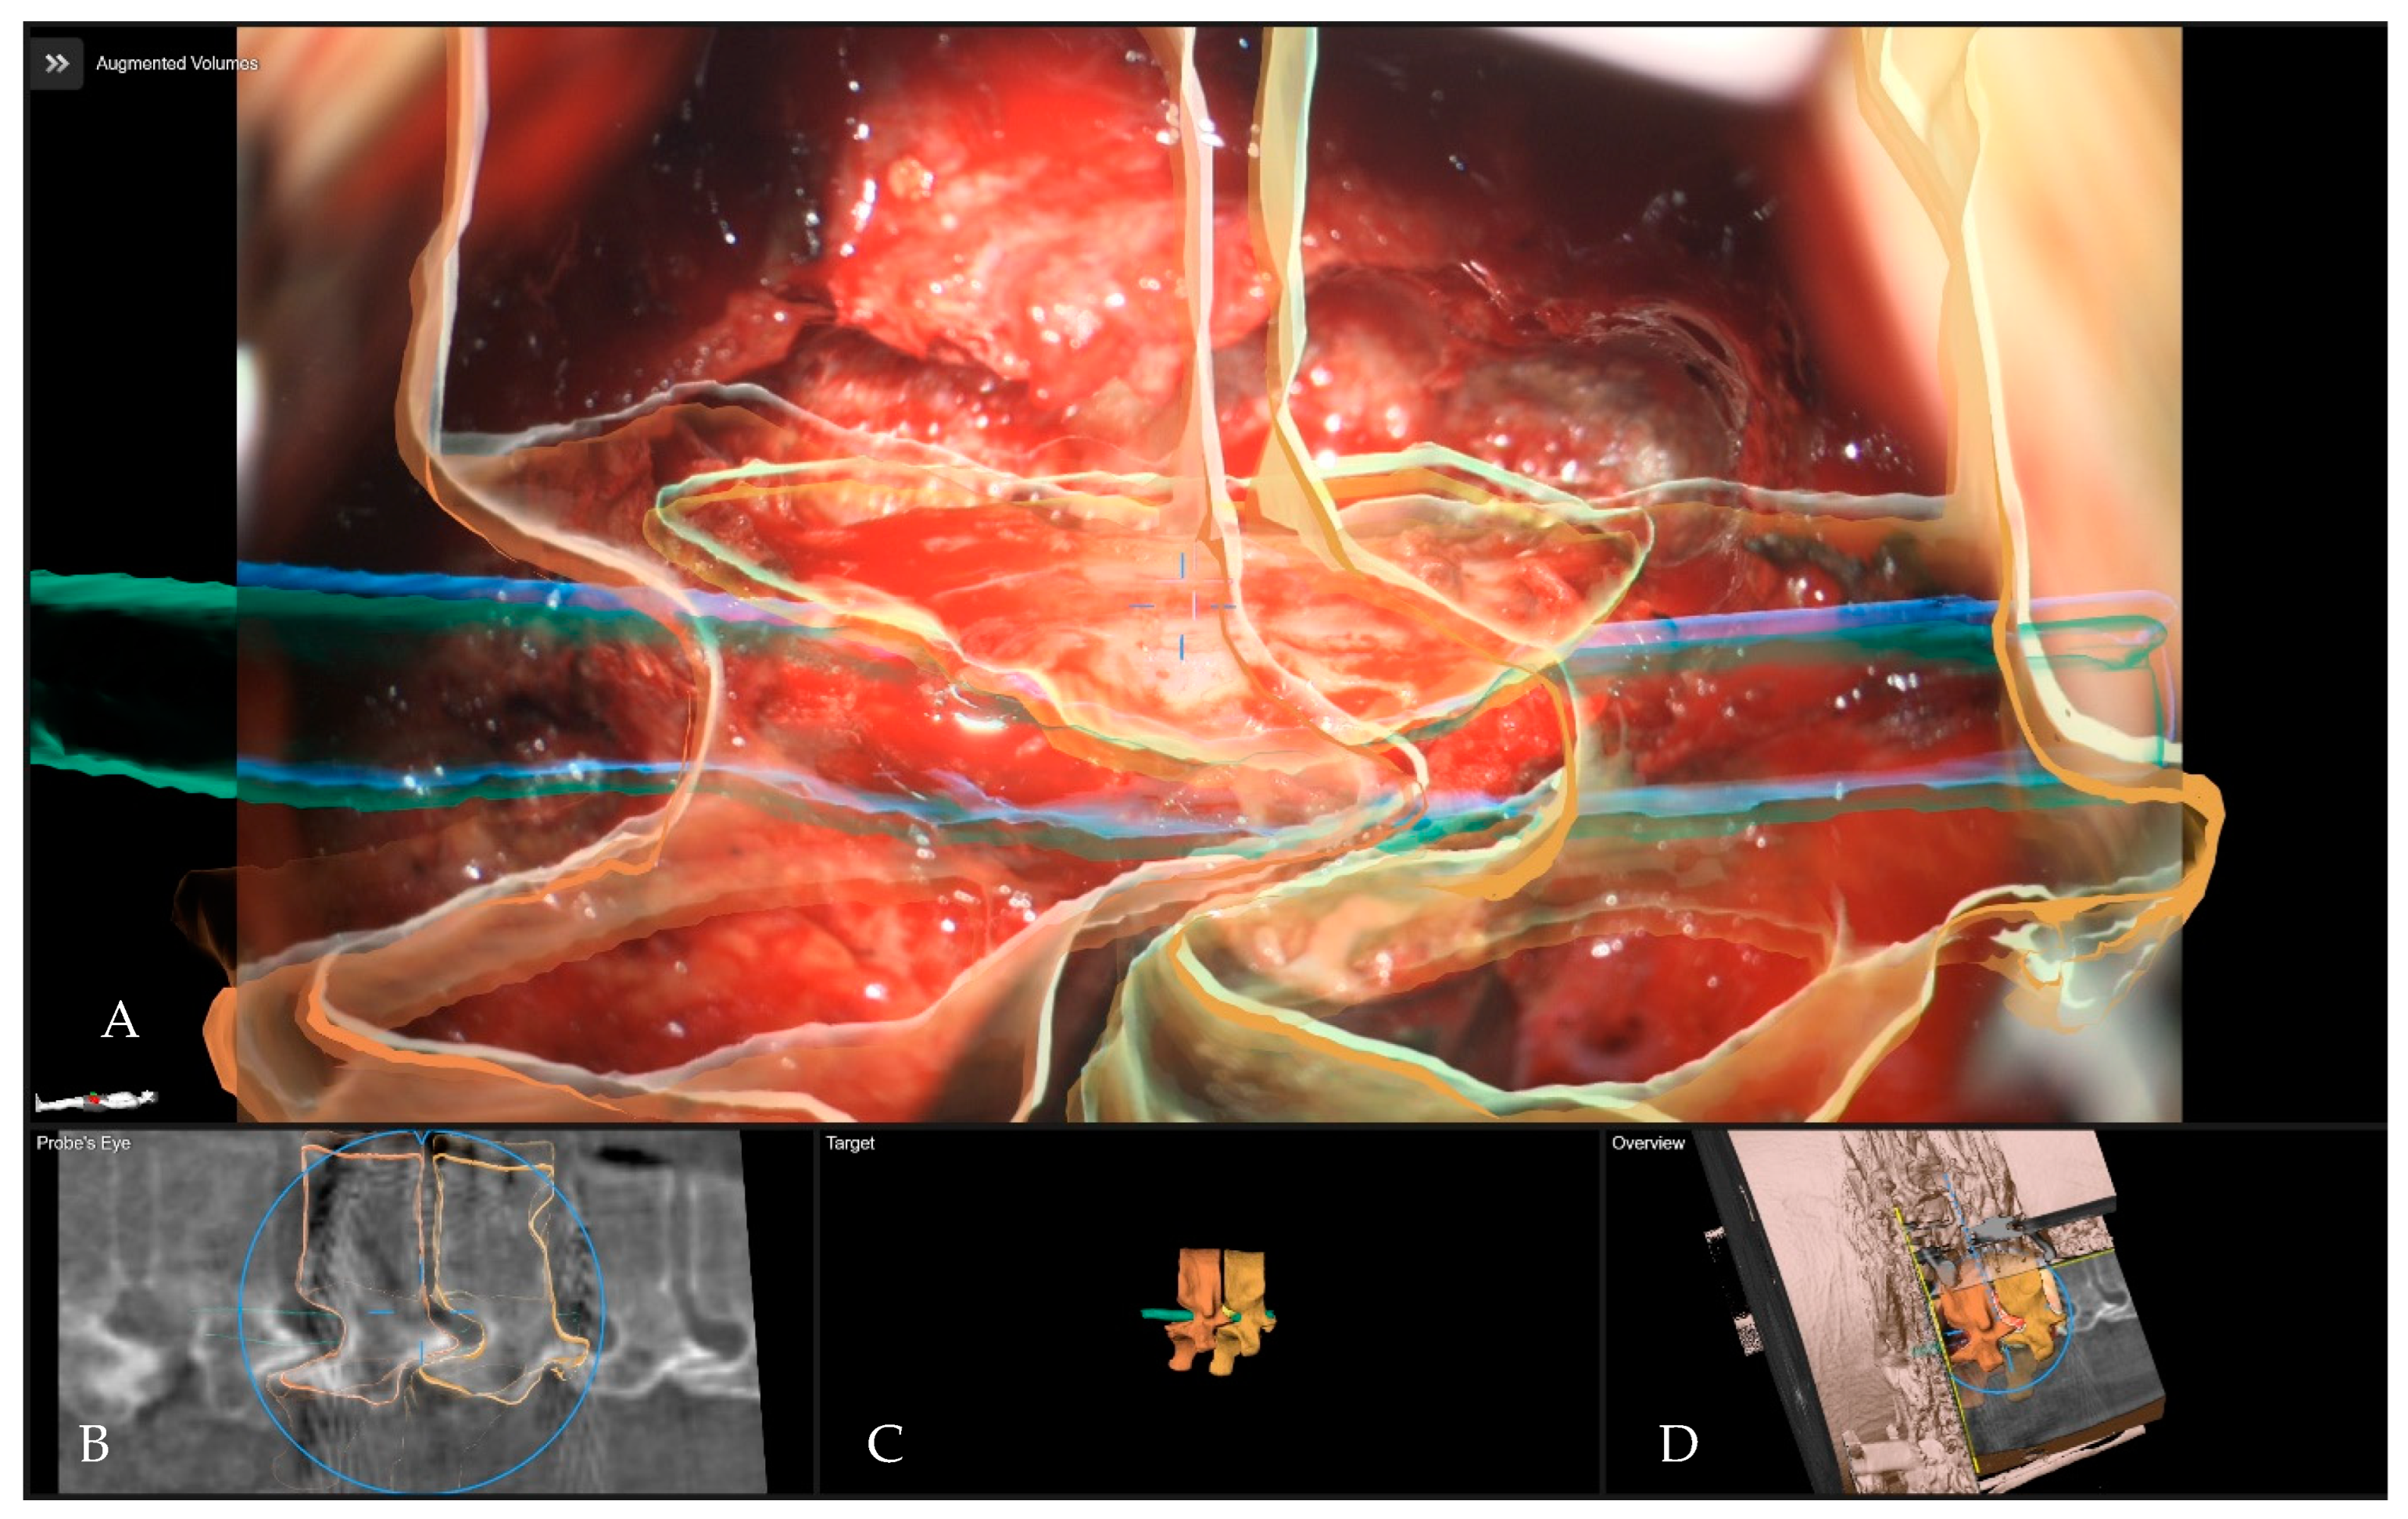

Surgical Treatment of Calcified Thoracic Herniated Disc Disease via the Transthoracic Approach with the Use of Intraoperative Computed Tomography (iCT) and Microscope-Based Augmented Reality (AR)

5.4. Applications of Augmented Reality for Degenerative Spine Surgery